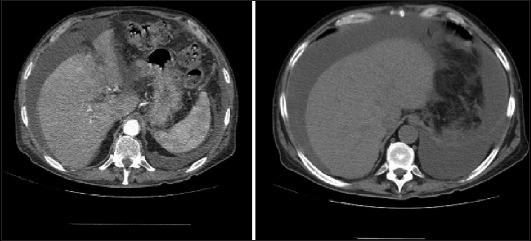

Pancreatic ascites is a rare condition characterized by the accumulation of high-amylase ascitic fluid in the peritoneal cavity. This condition is often associated with chronic pancreatitis, pancreatic trauma, or pseudocyst rupture. Because of its rarity and ill-defined clinical presentation, pancreatic ascites is often a diagnostic and therapeutic challenge in clinical practice. The current diagnostic criteria include an amylase level >1000 mg/dL, a protein level >3 g/dL, and a serum ascites albumin gradient <1.1 g/dL. The clinical features vary, but may include progressive abdominal distension, diffuse abdominal pain, weight loss and peritonitis. The management of pancreatic ascites remains controversial, and there is no consensus regarding the optimal approach. Conservative medical management, which includes nutritional support, pain control, therapeutic paracentesis and the use of somatostatin analogs, has been associated with a high failure rate and significant morbidity. Interventional therapies, such as surgery and endoscopic transpapillary stenting, have shown more promising outcomes. However, the choice between these methods is still debated, with some advocating for endoscopic approaches, because of their minimally invasive nature and reduced morbidity compared with surgical options. Endoscopic approaches remain underutilized in practice, probably because of the need for repeated interventions, the potential risks associated with endoscopic retrograde cholangiopancreatography, or a lack of skilled personnel. Although they show significant perioperative morbidity and mortality, surgical options provide definitive resolution of pancreatic ascites. Herein, we provide an updated review of pancreatic ascites, highlighting advances in diagnostic techniques and therapeutic approaches, and summarizing insights from recent clinical cases and retrospective studies.

胰源性腹水是一种罕见病症,其特征为腹腔内积聚高淀粉酶含量的腹水。这种病症常与慢性胰腺炎、胰腺创伤或假性囊肿破裂相关。由于其罕见性及临床表现不明确,胰源性腹水在临床实践中往往是诊断和治疗上的一大挑战。目前的诊断标准包括淀粉酶水平>1000毫克/分升、蛋白质水平>3克/分升以及血清腹水白蛋白梯度<1.1克/分升。临床特征各异,但可能包括进行性腹胀、弥漫性腹痛、体重减轻和腹膜炎。胰源性腹水的管理仍存在争议,对于最佳治疗方法尚无共识。保守药物治疗,包括营养支持、疼痛控制、治疗性腹腔穿刺放液及使用生长抑素类似物,其失败率较高且发病率显著。介入治疗,如手术和内镜下经乳头支架置入术,已显示出更有前景的结果。然而,这些方法之间的选择仍存在争议,一些人主张采用内镜方法,因为其微创性质以及与手术选择相比发病率较低。内镜方法在实践中的应用仍然不足,可能是因为需要重复干预、与内镜逆行胰胆管造影相关的潜在风险,或缺乏技术熟练的人员。尽管手术选择显示出显著的围手术期发病率和死亡率,但能为胰源性腹水提供确定性的解决方案。在此,我们提供胰源性腹水的最新综述,强调诊断技术和治疗方法的进展,并总结近期临床病例和回顾性研究的见解。